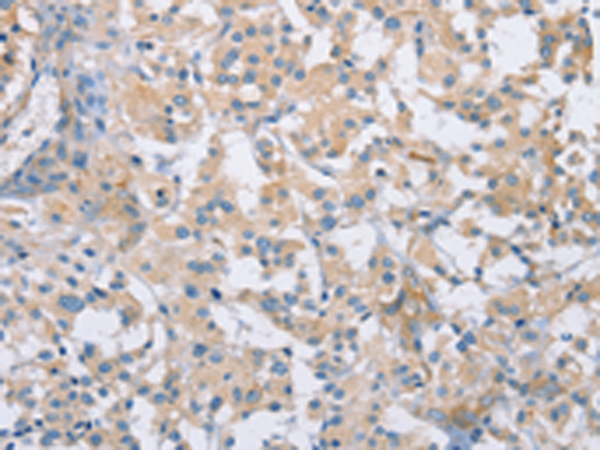

分类: 科研抗体货号: P04694别名: BSP1; JV41; BSP-1; JV4-1; MADH1; MADR1应用: IHC反应种属: Human, Mouse, Rat